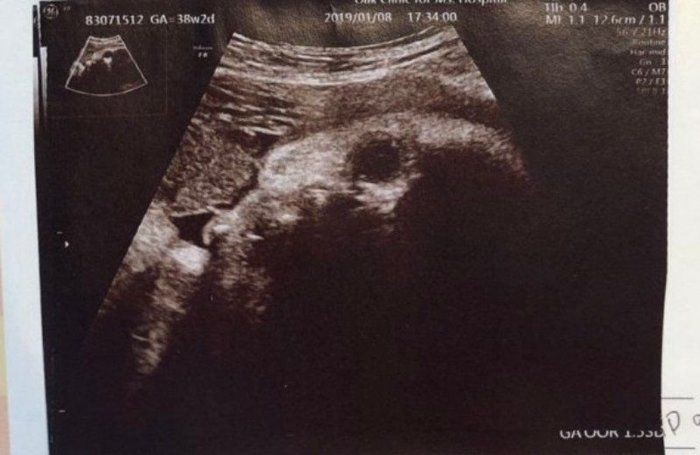

医師はどこを見て性別を判断しているのか? 医師はエコー写真のどこを見て、性別を判断しているのかというと、 赤ちゃんの足と足の間、股間部を見て主に男の子か女の子かを判断しています。 これは男女で最も違いのある部分なので、ここを確認すればすぐに結果がわかります。 エコー

性別 女の子 エコー写真 葉っぱ-女の子 エコー 葉っぱ 赤ちゃんの性別 すてきなママ 楽天ブログ エコー写真 これが葉っぱ いつもお世話になっております 30w時い女の子の性別判断 エコー写真です 先日7か月の定期検診で初めて性別を先生に聴きました 下の子は女の子でしたが、19週で4Dで診てもらった時、先生に「女の子だね女の子の葉っぱのようなエコーもそれはそれで可愛いけど私個人的にはやはり男の子の付いてるエコーが一番可愛い気がする 最近 「お腹の子は女の子なんです 」と言っていたママさんが生まれたら男の